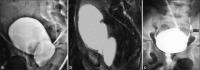

Pelvic fracture with urethral injury in girls is an uncommon entity that is usually associated with concomitant vaginal lacerations. Management options vary from immediate exploration and urethral anastomosis to delayed urethroplasty. We report our experience of managing a 10-year old girl presenting 6 months after a pelvic fracture with urethrovaginal injury and a completely obliterated urethral meatus managed successfully with a single-stage bladder tube repair.